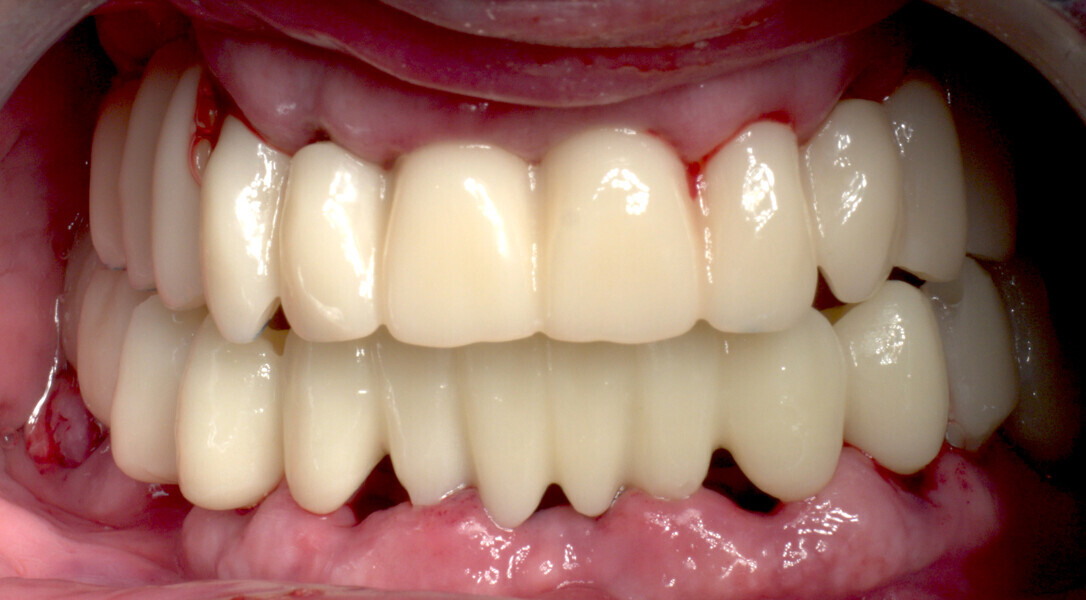

The fully digital Pro Arch protocol